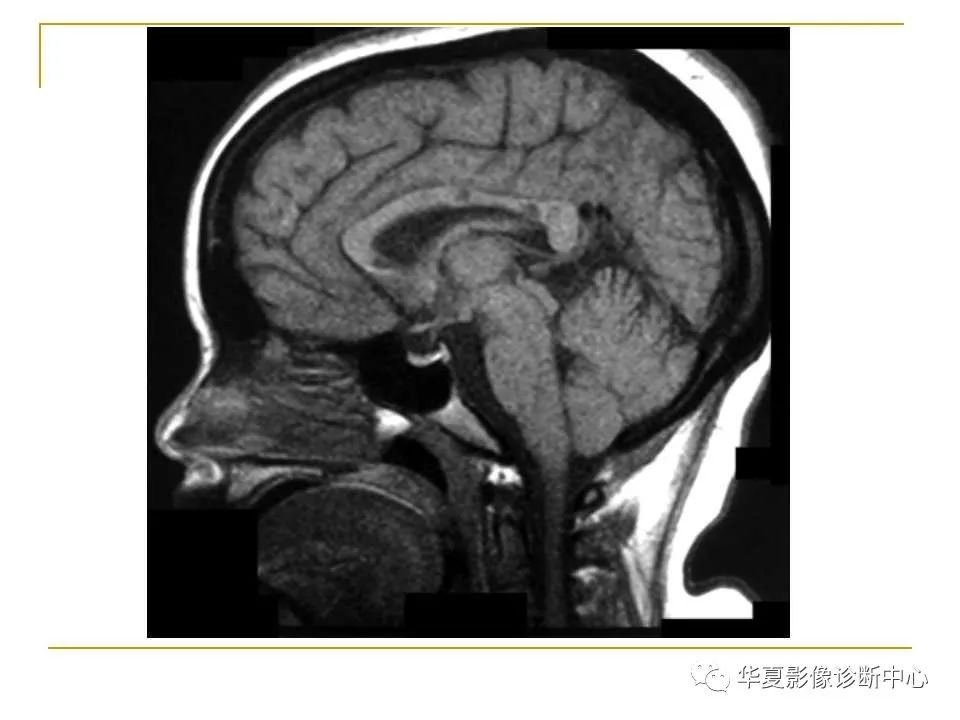

胼胝体解剖及病变大全